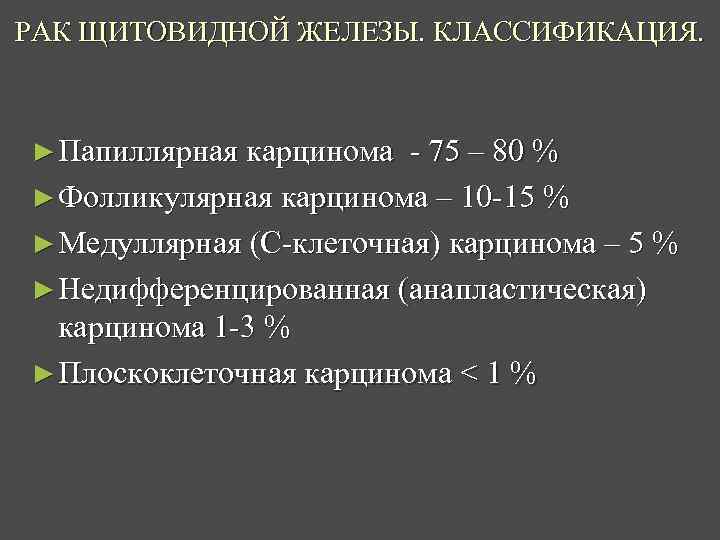

РАК ЩИТОВИДНОЙ ЖЕЛЕЗЫ. КЛАССИФИКАЦИЯ. ► Папиллярная карцинома - 75 – 80 % ► Фолликулярная карцинома – 10 -15 % ► Медуллярная (С-клеточная) карцинома – 5 % ► Недифференцированная (анапластическая) карцинома 1 -3 % ► Плоскоклеточная карцинома < 1 %